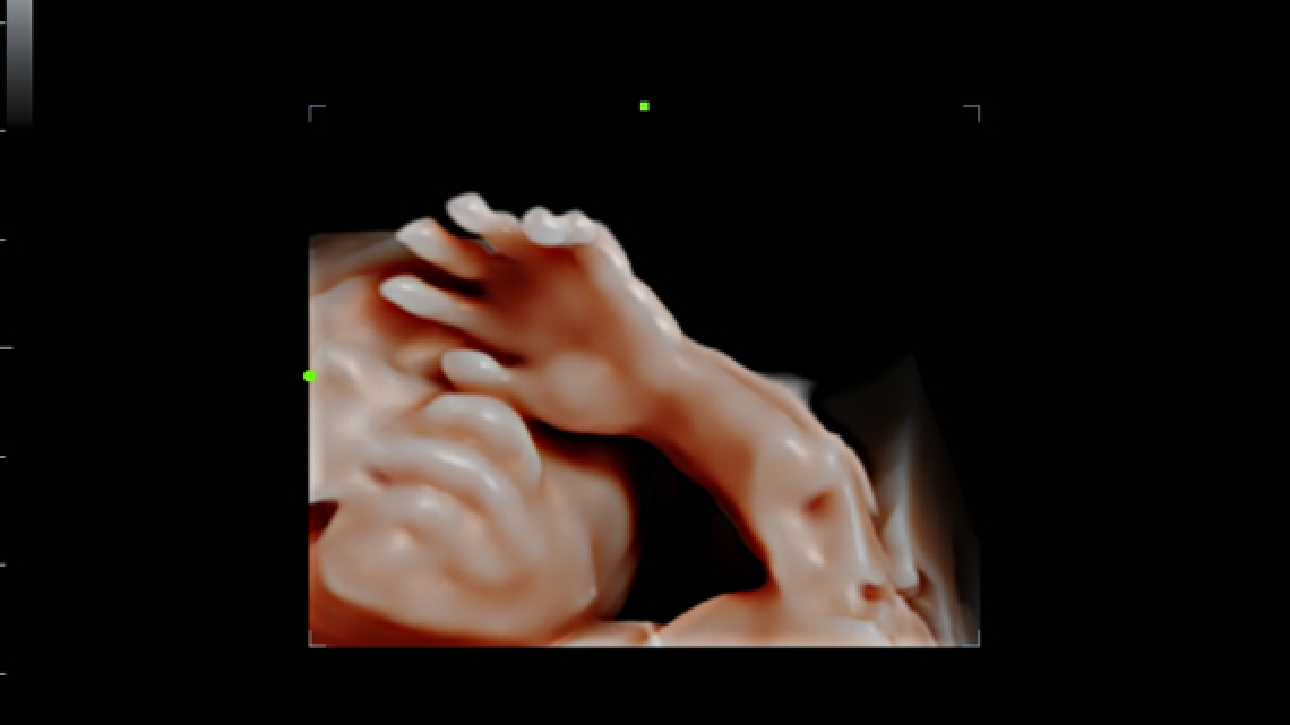

ImĂĄgenes clĂnicas